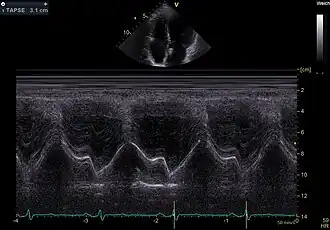

TAPSE

TAPSE ist eine Akronym für tricuspid annular plane systolic excursion, einen Messwert in der Echokardiografie mit dem die Kontraktionsfähigkeit (systolische Funktion) der rechten Herzkammer beschrieben werden kann. Hierbei wird im apikalen 4-Kammer-Blick mit dem M-Mode die Bewegung des lateralen / anterioren Trikuspidalklappenanulus gemessen als Maß für die Verkürzung des rechtsventrikulären Myokards bei der Kontraktion.

Als normal werden Werte über 1,7 cm angenommen.[1]